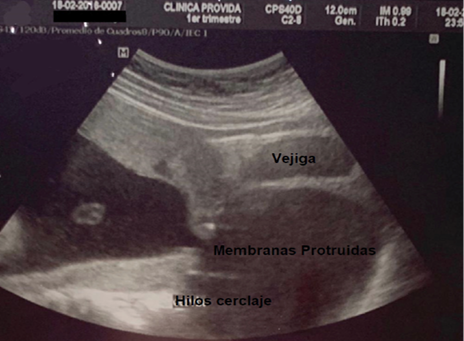

G1: aborto a las 20 semanas de gestación. G2: aborto a las 20 semanas de gestación. G3: aborto a las 21 semanas de gestación a pesar de haberse realizado cerclaje vaginal técnica McDonald a las 12 semanas por el servicio de ginecología-obstetricia del Hospital Básico Provida; se observa en la Figura 3 los hilos del cerclaje con la protrusión de membranas ovulares en vagina el día del aborto. G4: actual, edad gestacional 13 semanas por fecha de ultima menstruación (FUM).